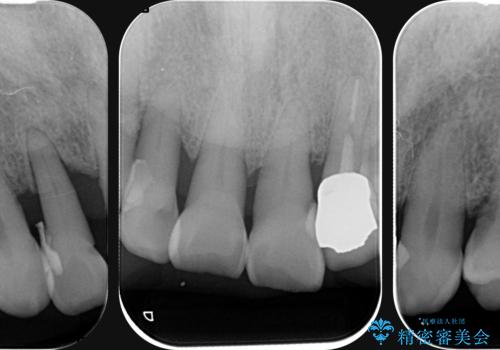

- 前歯の見た目をなんとかしたい、とセラミック治療を希望され来院されました。

セラミック治療を行う前に歯周病の問題を解決すべく歯周外科を行い歯周ポケットを除去し整備したのちセラミックブリッジ・クラウンの製作を行います。